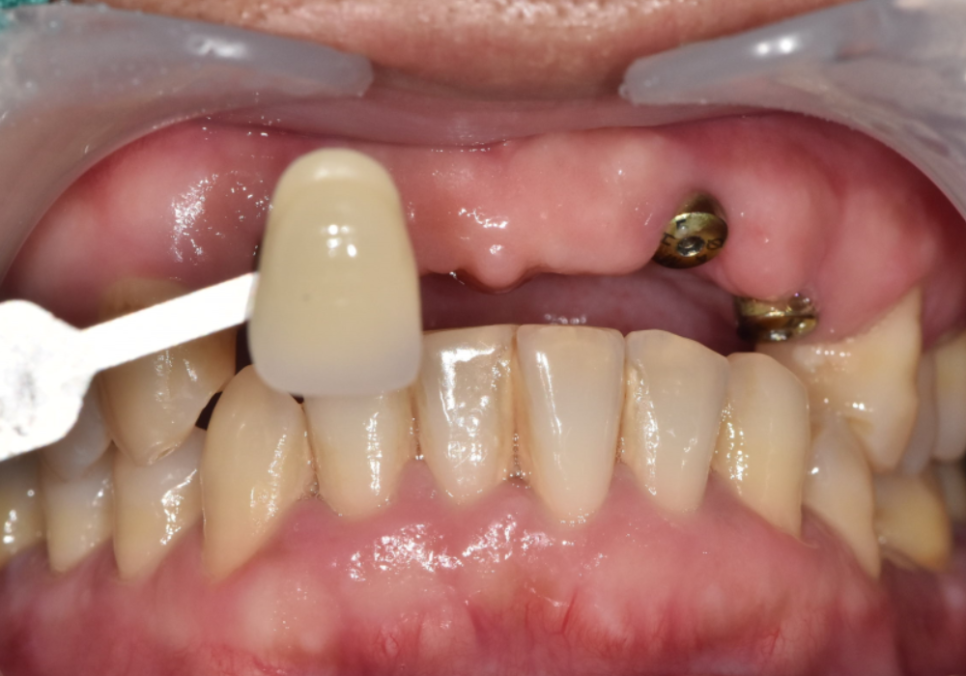

그 후, 단단하게 고정된 것을 확인한 뒤

정밀 스캐너로 본을 떠서

최종 지르코니아 보철물을 제작해 드렸습니다.

특히, 이전 보철물을 사용하실 때

앞니가 유독 튀어나와 보였다고 하셔서,

이 부분을 충분히 고려하여

정교하게 보철을 제작하도록 신경썼는데요~